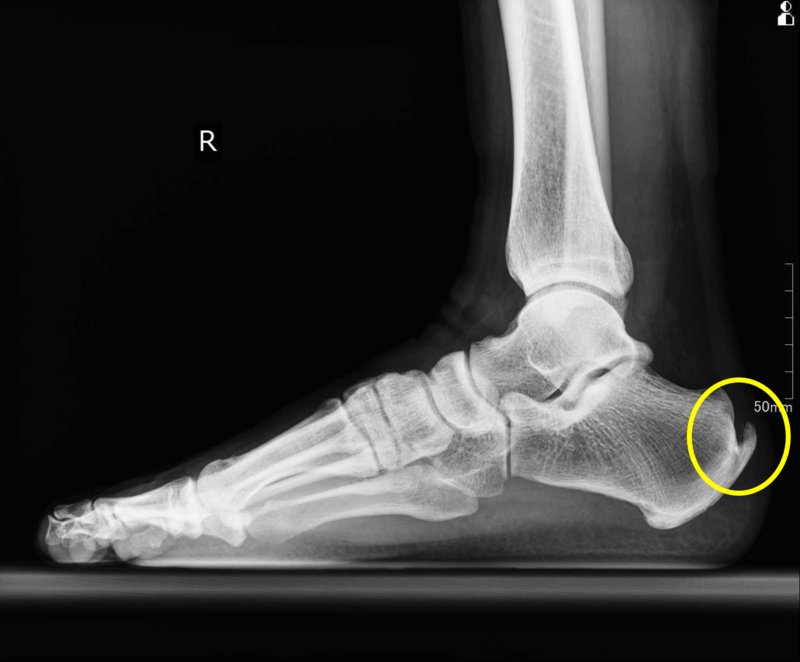

アキレス腱の踵骨付着部に骨棘形成が確認できます(左図:患側 右図:健側)

MRI:アキレス腱の踵骨付着部・踵骨骨棘部が白くなっており、変性を認めます